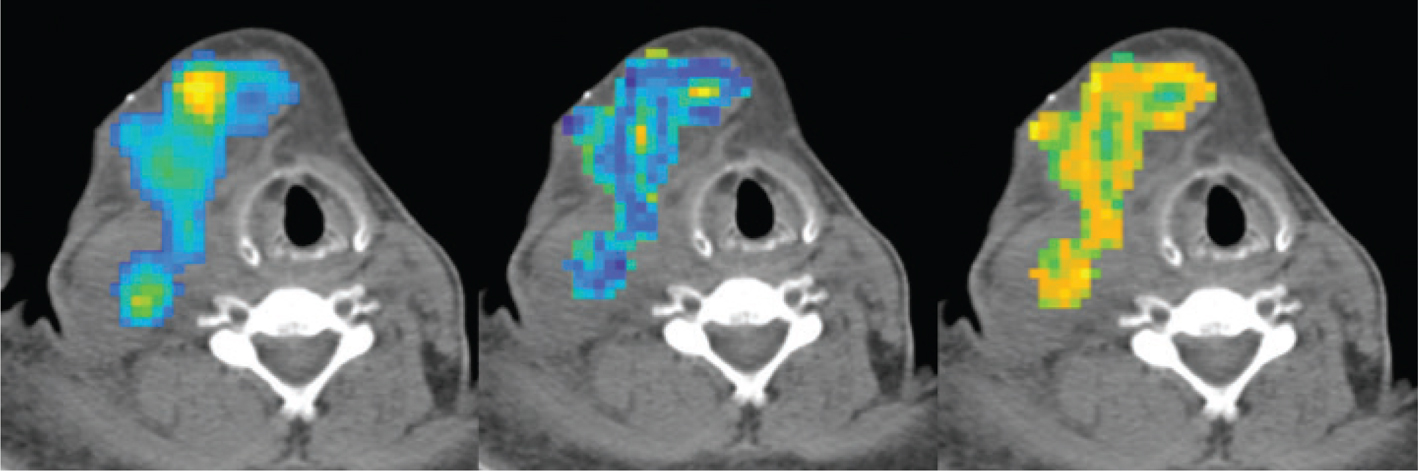

One potential approach to override these problems is to associate other features derived from imaging. A variety of mathematical methods can be used to describe the variability in the distribution of 18FDG uptake (as well as the variability in tissue density), resulting in the identification of several quantitative and semi-quantitative imaging features. This approach as a whole is termed radiomics (Figure 1). In other words, radiomics refer to the extraction of measurable features that derive from the conversion of images into mineable data and to their subsequent analysis. The radiomics process ends testing the correlation of the image features with the patient clinical characteristics and outcome (28). The underlying hypothesis of radiomics is that these quantitative image features related to the shape, morphology and heterogeneity of the lesion reflects the biological properties of the tumor. An example of different radiomics features on a patient’s lesion is shown in Figure 2.

Fig 2

Figure 2. Example of different radiomics features (colored) over-imposed to the CT of a lymphomatous lesion in a DLBCL patient. SUV on the left, emphasis at the center and contrast to the right.